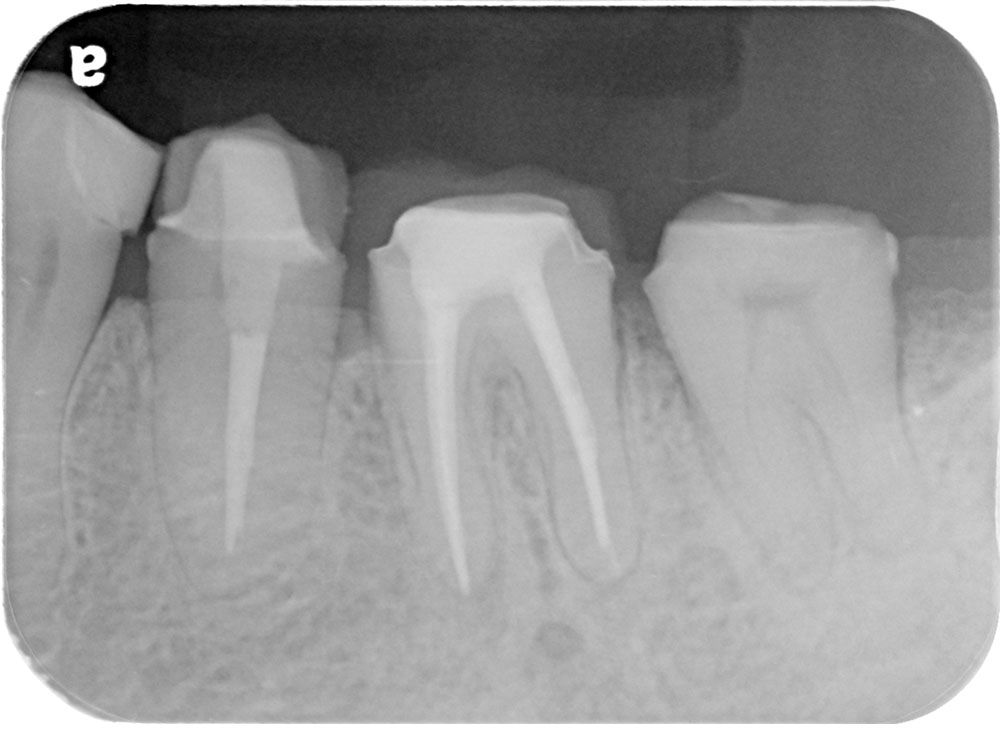

術前

術後

世代・性別

40代女性

主訴

ずっと痛い、噛むと特に痛い、前医でもうこれ以上はできないと言われた

治療内容

根管治療

治療期間

2ヶ月

治療費

保険適応内

治療のリスク

治療中または治療後に、一時的な痛みや腫れが生じることがある